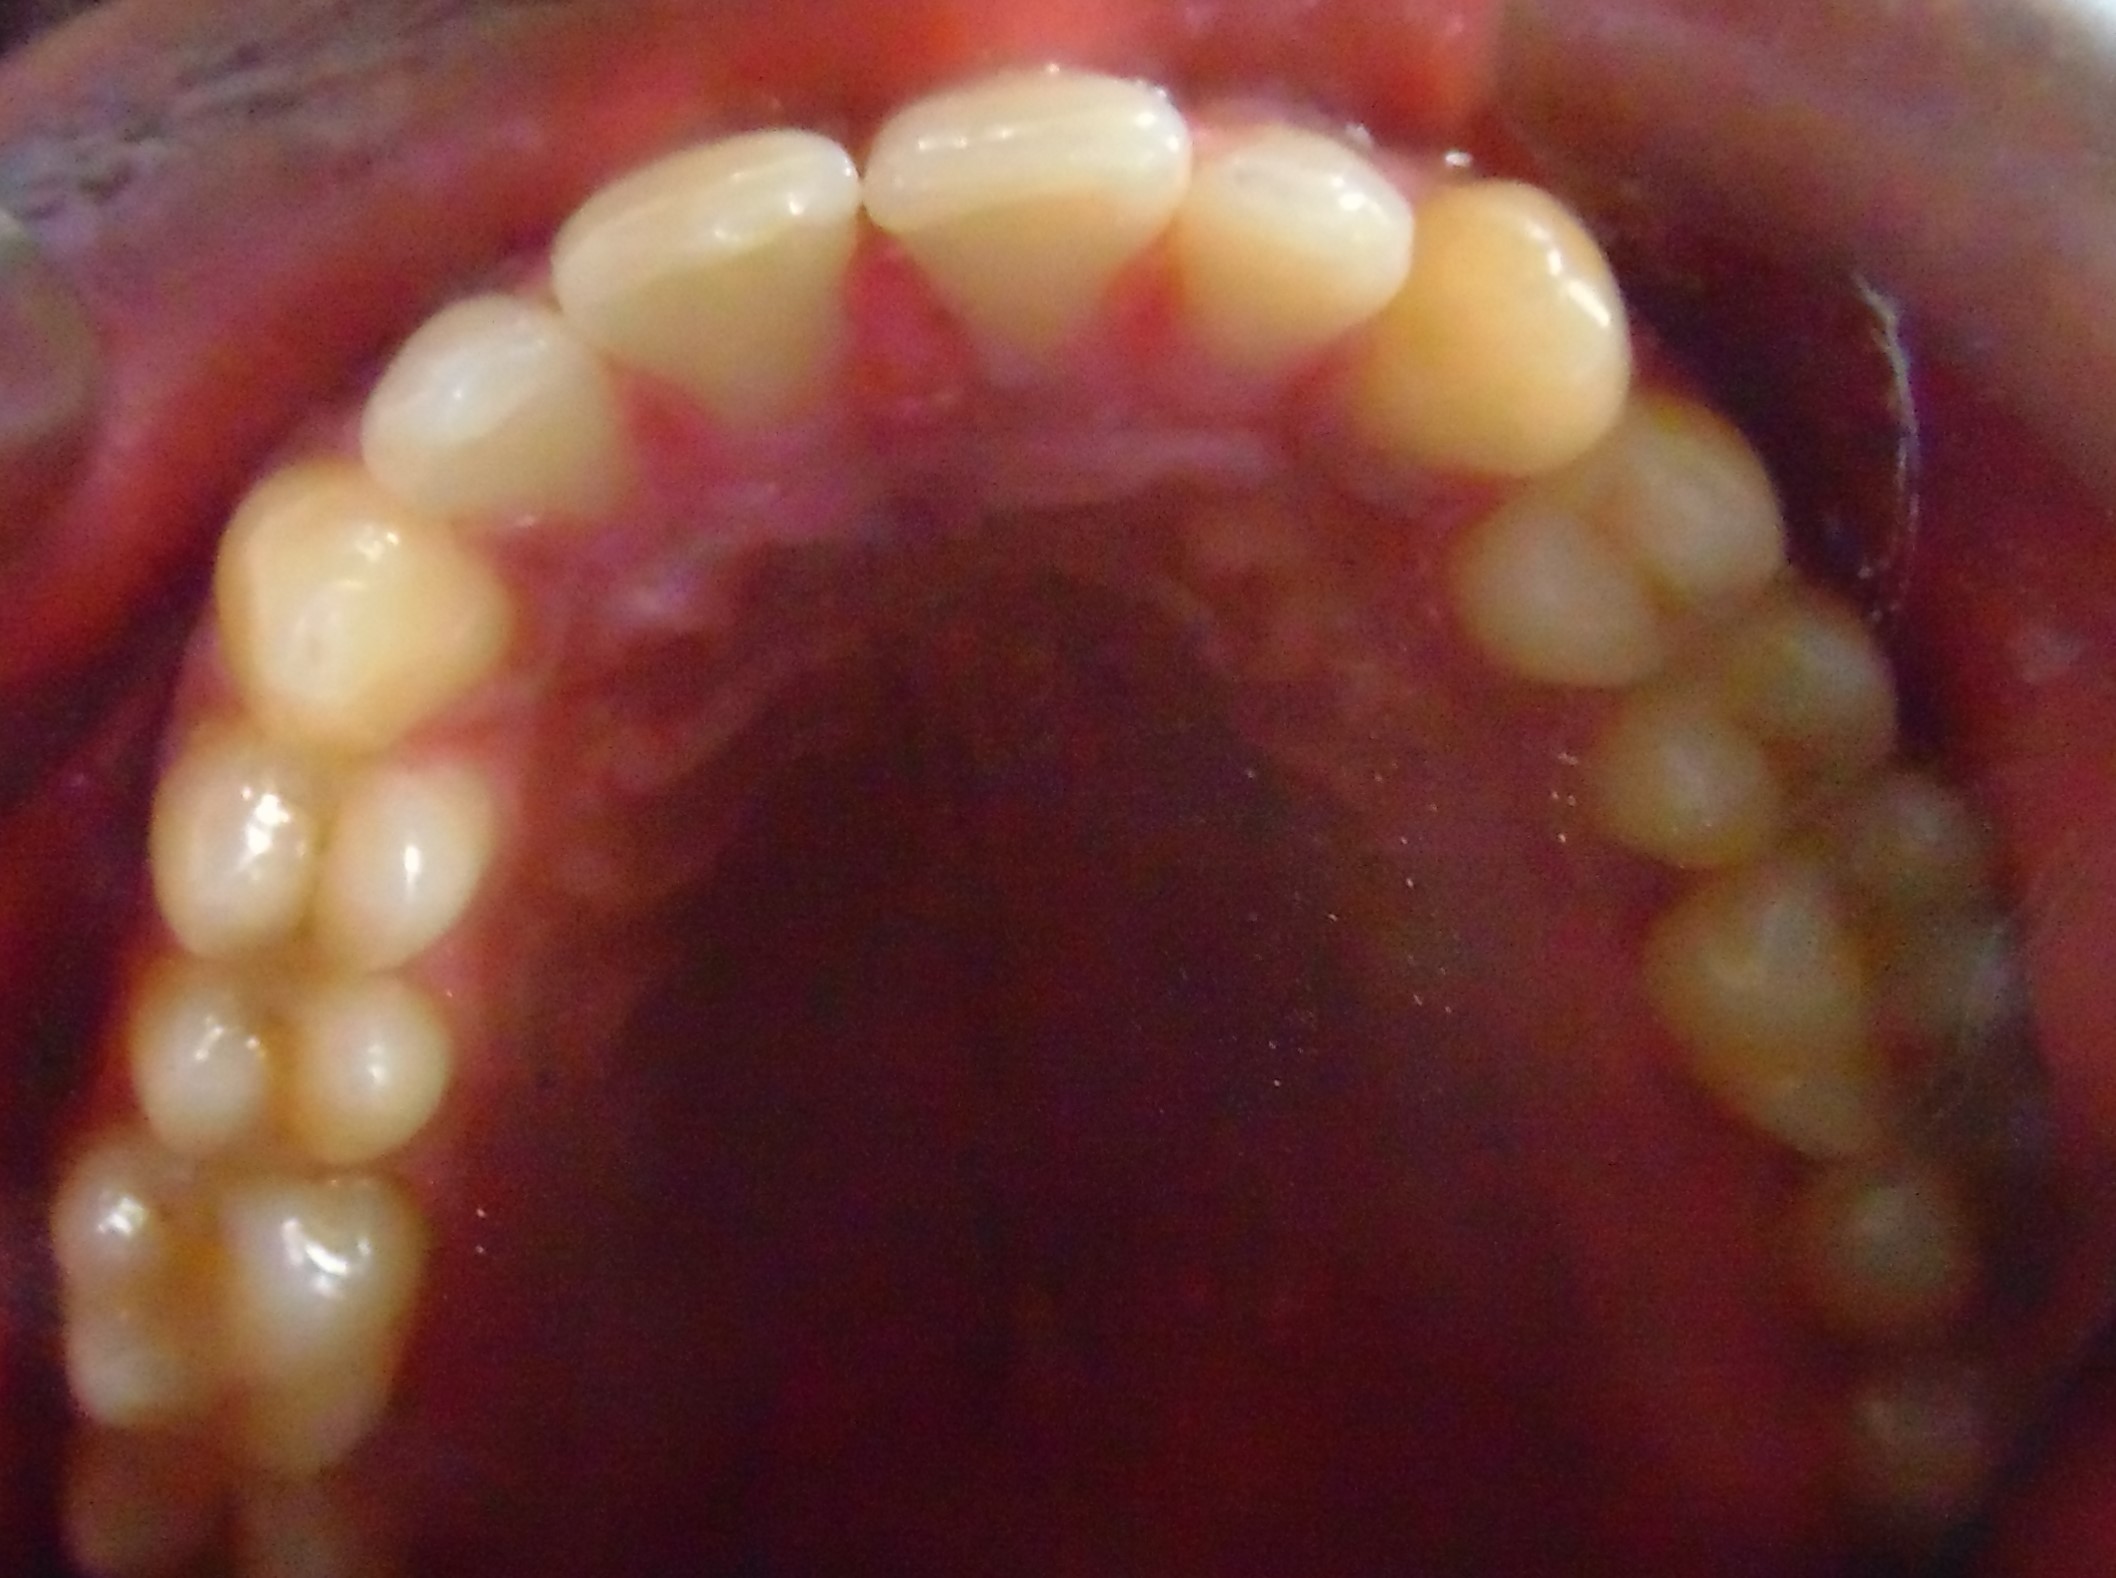

After

Image 2